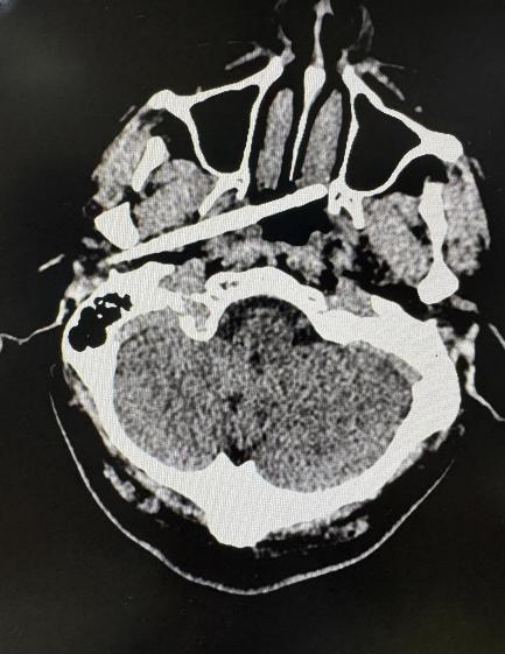

筷子从外耳道上方插入,穿透侧颅底-咽旁间隙,直抵鼻咽部,筷子尖端距离颈内动脉仅5毫米……1月10日,患者陈先生经紧急转诊至珠江医院,创伤中心迅速开启手术“绿色通道”,启动多学科会诊,经耳鼻咽喉头颈外科中心于超生主任医师团队2小时手术,最终顺利取出这双夺命的筷子。

东莞45岁男子在与人争执时,一根筷子从耳部插入颅底,筷子被折断,断端残留体内。更令人揪心的是,筷子不仅穿透了耳部骨质,筷子尖端距离颈内动脉仅5毫米——这是大脑供血的主干线之一,一旦破裂,可导致瞬间大出血死亡。

“筷子穿透路径紧贴咽鼓管旁的颈内动脉水平段,必须警惕迟发性假性动脉瘤等继发风险。”经多学科深入讨论,制定了“内镜联合开放手术”方案。手术安排在复合手术室进行,如不慎出现颈内动脉损伤破裂大出血,脑血管外科可迅速介入,植入支架控制出血,为安全取出异物提供双重保障。